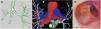

(A) Synapse-3D software CT reconstruction of the CT scan demonstrating the membrane at intermediate bronchus (black arrow) and the presence of additional bronchi distal to it (white arrow). (B) Synapse-3D software CT reconstruction illustrating right pulmonary artery hypoplasia. (C) Bronchoscopic imagen showing a translucent membrane at intermediate bronchus (black arrow) and the entrance to the right upper lobe (white arrow).

A 34-year-old woman with asthma and recurrent exacerbations underwent chest computed tomography, which revealed right lung volume loss and hyperlucency, along with hypoplasia of the right pulmonary artery, consistent with Swyer–James–MacLeod syndrome (SJMS). Additionally, distortion of the central right bronchial tree and a probable membranous structure in the intermediate bronchus (IB) were identified. A three-dimensional (3D) reconstruction using the Synapse 3D system (version 6.7, Fujifilm, Japan) confirmed obstruction at the IB level with preserved distal bronchial continuity (Fig. 1A and B). Flexible bronchoscopy confirmed the presence of a membranous obstruction in the IB, with synchronous motion during respiration, suggesting residual distal airway ventilation (Fig. 1C). Based on these findings and considering the likely post-infectious etiology of SJMS, an acquired origin of the bronchial web was suspected and a conservative approach was adopted. Nevertheless, close clinical and radiological follow-up was planned, and endoscopic puncture of the membranous structure will be considered should the patient develop symptoms warranting it. While SJMS is usually managed conservatively, surgical approaches may be considered in selected cases [1–3]. In cases of complex airway anatomy, combining Synapse 3D with bronchoscopy enhances diagnostic precision and supports personalized management [4,5].